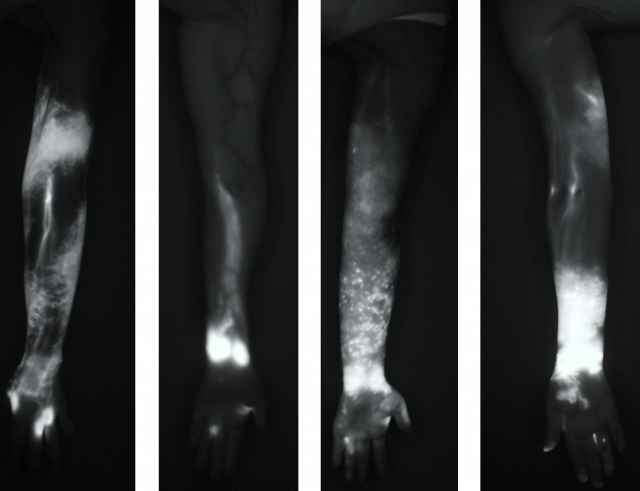

림포스코프 ICG로 림프부종 환자의 팔을 촬영한 이미지. 형광염료가 림프관 위치와 림프액이 쌓인 위치를 보여준다. 부산대병원 제공 림포스코프 ICG로 림프부종 환자의 팔을 촬영한 이미지. 형광염료가 림프관 위치와 림프액이 쌓인 위치를 보여준다. 부산대병원 제공

최근에는 인체에 무해한 형광염료인 인도시아닌그린(ICG)을 이용해 얕은 림프관의 흐름을 확인하는 인도시아닌그린 림프조영술이 함께 시행된다. 부산대병원은 이를 위해 국내 최초로 데이터 기반 림프부종 전용 촬영기기인 '림포스코프 ICG(LymphoScope ICG)'도 개발했다.

림포스코프 ICG는 인도시아닌그린 주입 후 발산되는 근적외선을 통해 얕은 림프관을 촬영해 림프부종의 주요 손상 부위인 얕은 림프관의 손상 정도와 기능을 평가한다. 방사선 노출이 없고, 장기간 촬영이 가능하다.

윤진아 교수는 "인도시아닌그린 림프조영술은 진단뿐 아니라 예후 관리와 맞춤형 치료에도 활용된다"며 "부종이 생기기 전에 림프부종을 조기에 진단하고, 치료 후에도 호전 여부를 객관적으로 평가해 추후 치료 계획을 수립할 수 있는 장점이 있다"고 설명했다.

림프부종 환자는 환자마다 림프관 손상 부위와 부종의 양상이 다르다. 인도시아닌 림프조영술을 통해 환자 개별 림프 상태를 확인하는 '림프 지도 만들기(Lymphatic mapping)'를 하고 나면, 그에 맞춰 마사지로 체내 림프액의 흐름을 유도하는 도수 림프 배출법를 포함해 여러 치료 방법을 적용하는 복합림프물리치료를 시행하게 된다.